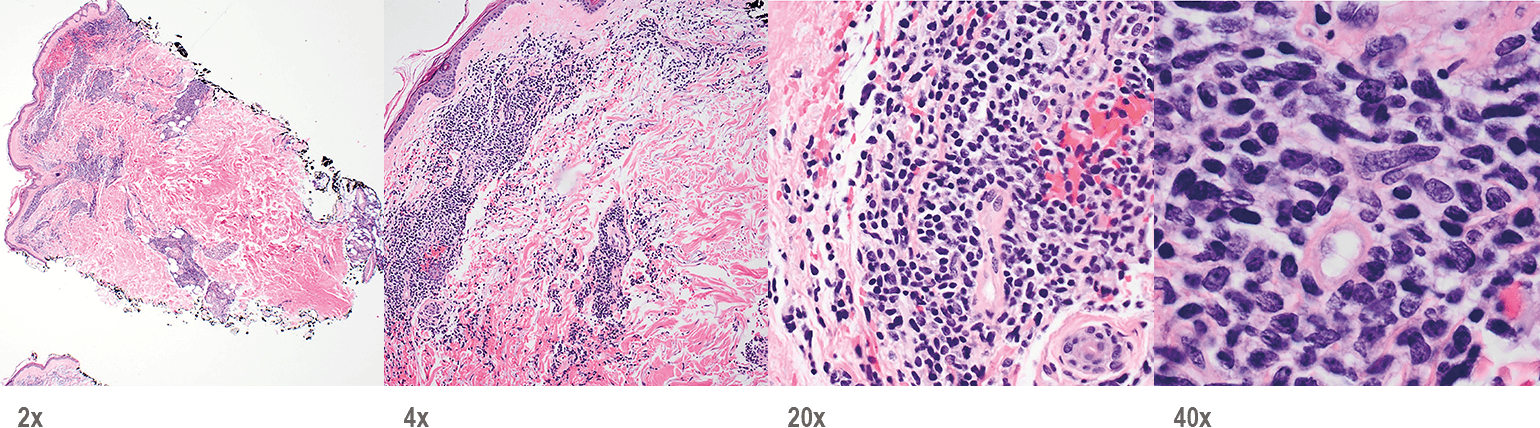

Recognizing BPDCN: Morphology

Punch biopsy of a skin lesion showing BPDCN Punch biopsy of a skin lesion showing BPDCN

Skin

Punch biopsy of a skin lesion showing BPDCN (H&E stain, x40) and (inset) medium-sized malignant cells spare the epidermis (H&E stain, x1000).11

Main morphologic features of BPDCN biopsy

• Diffuse, monomorphic infiltrate1

• Medium-sized blast cells with irregular nuclei1

• Fine chromatin1

• At least 1 small nucleolus1

• Malignant BPDCN cells do not typically infiltrate the epidermis4

BPDCN with low-density infiltrate may mimic an inflammatory condition4

BPDCN with low-density infiltrate BPDCN with low-density infiltrate

• Cutaneous cases with minimal involvement show periadnexal and perivascular infiltrate, clustering in the superficial to mid dermis12,13

• Cytology, in association with flow cytometry immunophenotyping and clinical history, can help obtain an accurate diagnosis of BPDCN14